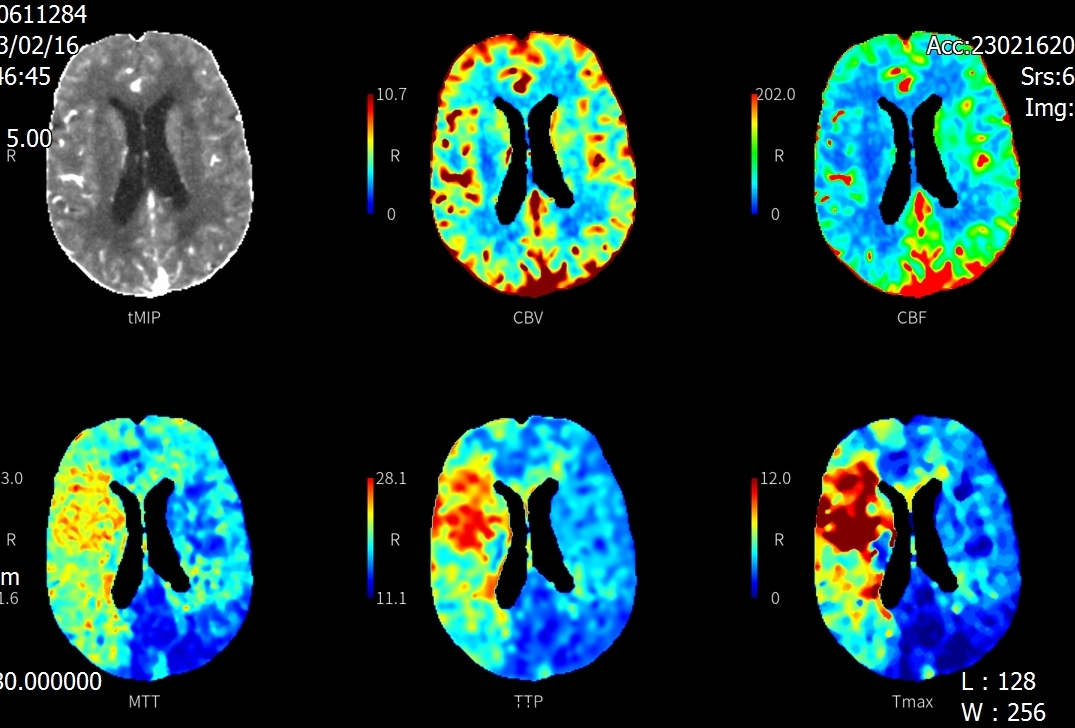

2月16日,72岁的黄先生在家中突发左侧肢体无力伴言语不清,家属将其送至我院急诊科就诊,卒中团队会诊后考虑急性脑卒中,NIHSS评分:20分,并立即护送患者至放射科。放射科医技护启动绿色通道,在3分钟内完成一站式卒中CT检查,并对脑CT灌注(CTP)及CT血管造影(CTA)图像进行快速评估:可见患者双侧颈内动脉及右侧大脑中动脉均闭塞(图1);CTP显示患者右侧大脑半球血流灌注减低(图2),但存在较大面积的缺血半暗带(图3),这提示如果能及时改善血运,可挽救大部分缺血脑组织,显著缩小脑梗死的范围,进而改善患者预后。基于可靠的影像证据,神经内科卒中团队当机立断通过急诊介入手术成功取栓并扩张颈内动脉,患者右侧大脑半球及时恢复了血供。术后第2天患者四肢、言语功能恢复良好,NIHSS评分:7分。术后第3天后MRI复查显示脑梗死范围远远小于术前低灌注区域(图4)。

图2:CTP示右侧大脑半球血流灌注减低